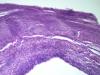

Образование левой ветви легочного ствола |

Макро фотографии к сожалению нет. Был фрагмент легочного ствола с бифуркацией, один сосуд с обычными стенками, макро без изменений, в второй неравномерно утолщен, как бы часть сосудистой стенки обычная, а часть утолщена и частично выпирала в просвет.

Эндотелизированный и реканализованный тромб трудно с чем-либо спутать. Теперь надо двигаться дальше: катамнез, причина, источник ТЭЛА и т.д. К примеру, при АФС ответ очевиден, а при "ТЭЛА" вследствие патологии ЛА - думать о сосудистом процессе.